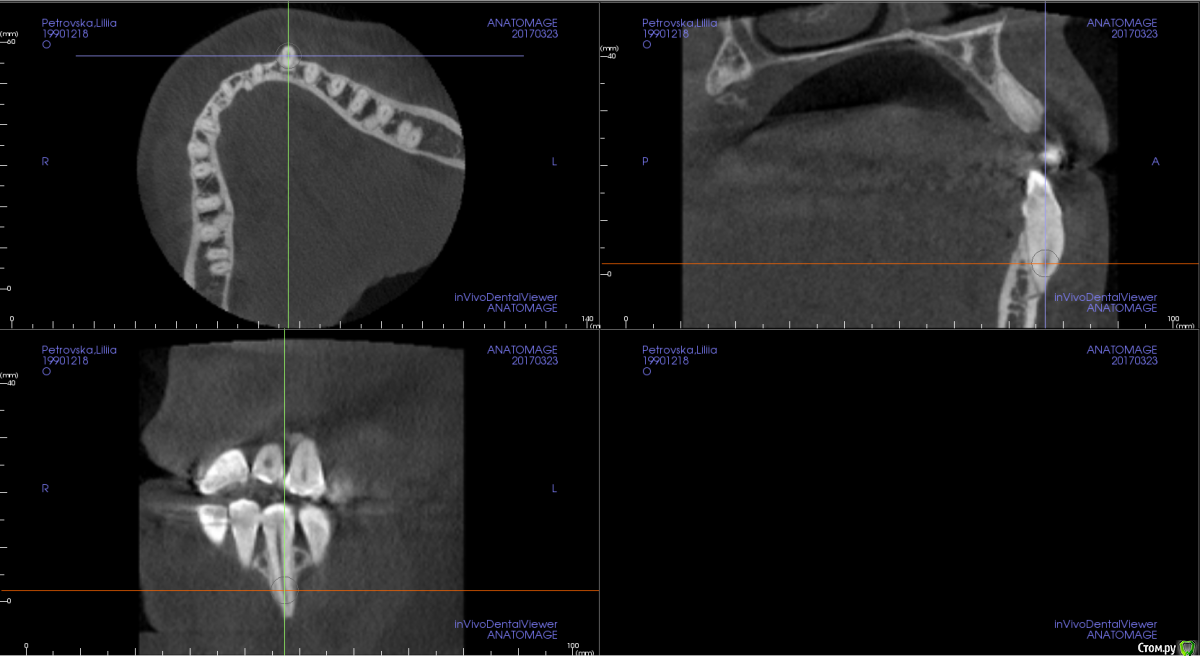

m.d.n Опубликовано 20 марта, 2017 Поделиться Опубликовано 20 марта, 2017 срезы кт покажите . на чем остановились Ссылка на комментарий

Opdihatop Опубликовано 26 марта, 2017 Автор Поделиться Опубликовано 26 марта, 2017 Прошу:313233414243 Ссылка на комментарий